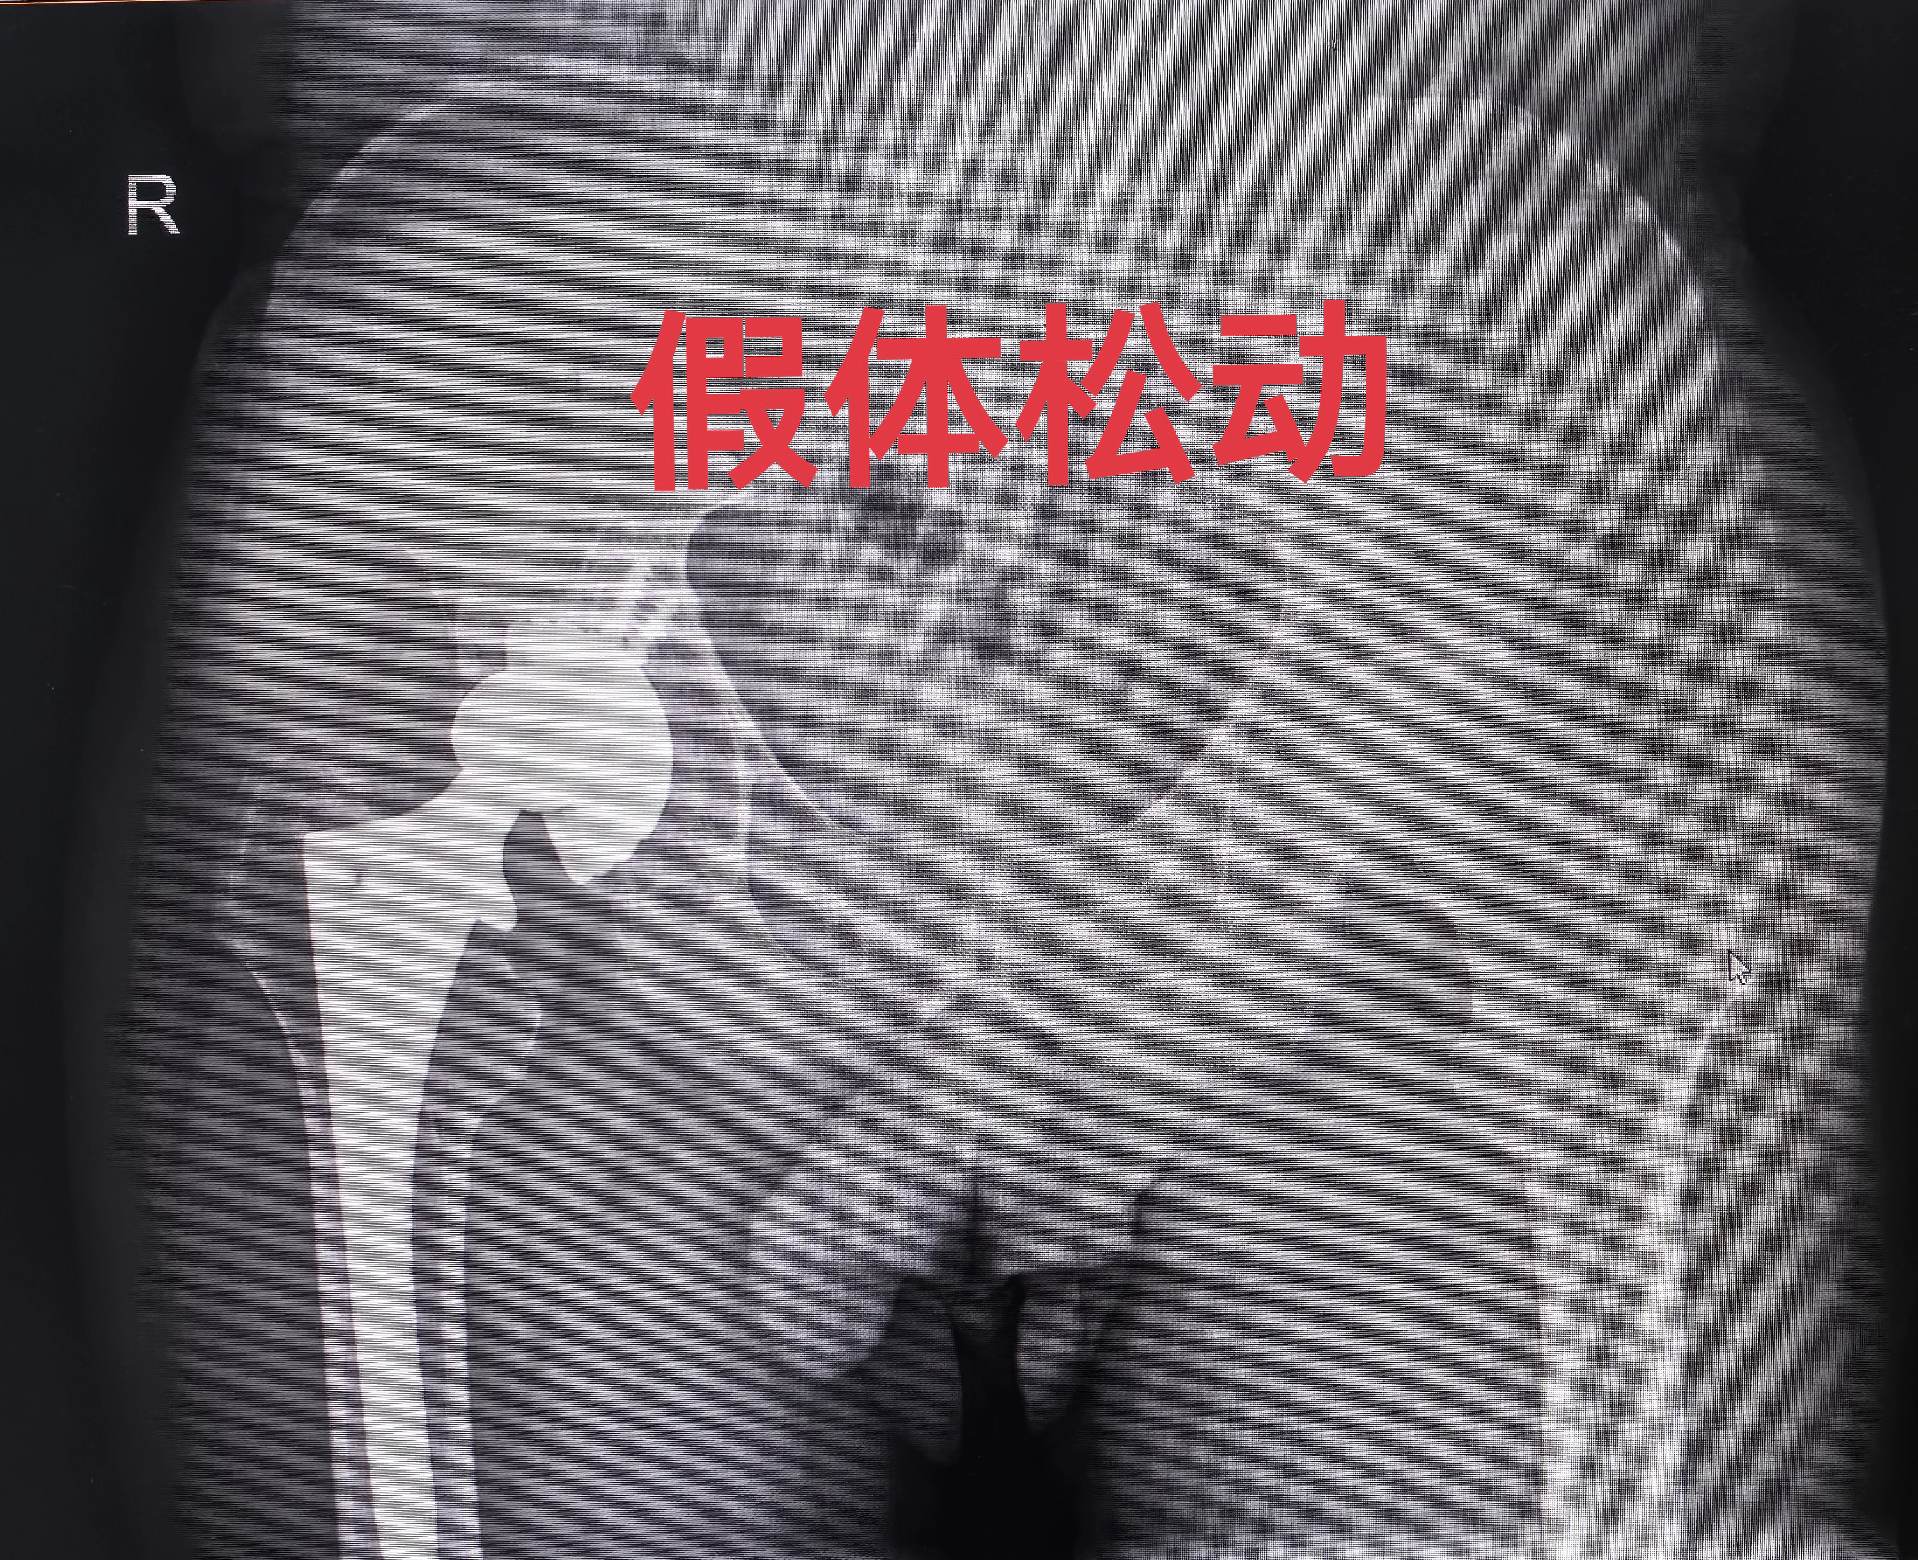

髋关节置换术后假体松动。髋关节置换术后假体松动,一定要做髋关节ct,此例髋臼内壁缺损明显,好在髋臼环完整,缺损处植骨,髋臼初始稳定性良好,术后两天正常下床,患者满意度很高🌹